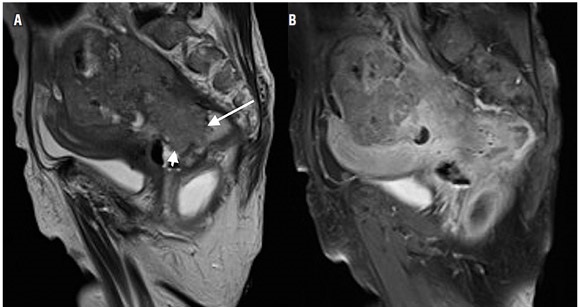

La estadificación del tumor depende directamente de su relación con la capa muscular propia y de la invasión con los órganos adyacentes (8). Un tumor T1 es aquel que se encuentra confinado a la mucosa, un tumor T2 es el que se extiende hasta la muscular propia (figura 3), un tumor T3 invade y se extiende más allá de la muscular propia (T3 temprano menor de 5 mm o T3 avanzado mayor de 5 mm) (figuras 4 y 5) y un tumor T4 es aquel que invade los órganos pélvicos (figura 6) (15). Los vasos pélvicos, la fascia parietal pélvica y la fascia mesorrectal no son considerados órganos (8).

Para evitar errores debidos al volumen parcial, las imágenes deben ser obtenidas en un plano perpendicular a la capa muscular (8), reconociendo la capa muscular propia como una estructura hipointensa (negra), delgada, que rodea el recto (8). Dentro de los signos que sugieren una extensión más allá de la muscular propia (T3 avanzado) (figura 5) se encuentra la ulceración tumoral, un tumor que ocupe más de la mitad de la circunferencia, un tumor con un mayor compromiso longitudinal, metástasis ganglionares o a distancia (8).

Hacer la diferencia entre lesiones estadio T2 y T3 no siempre es sencillo, ya que las reacciones desmoplásicas o los cambios de fibrosis generan especulación de la grasa perirrectal y no siempre es posible diferenciar cuando hay o no presencia de componente tumoral en estas lesiones, lo que lleva a una sobrestimación de la estadificación (14,18,23,30-32). Esta situación es particularmente importante en pacientes que hayan sido tratados con radioterapia; en este escenario la presencia de lesiones nodulares, a diferencia de la espiculación, favorece el diagnóstico de residuo o recidiva tumoral sobre los cambios por radioterapia.

Los órganos pélvicos más frecuentemente comprometidos durante el cáncer rectal son el útero, la vagina, la próstata y las vesículas seminales (15). La valoración del compromiso tumoral de estas estructuras, así como de la fascia presacra y el compromiso de los nervios sacros, tienen un significado en cuanto a la planeación quirúrgica, especialmente porque al afectar alguno de estos últimos vuelve el tumor irresecable (15).

El esfínter anal se compone de un esfínter interno de músculo liso, continuación de la capa circular del recto, y un esfínter externo de músculo estriado compuesto por el elevador del ano y una extensión del músculo puborrectal (15). La ubicación del tumor y el esfínter anal deben ser visualizados en imágenes coronales donde sea posible identificar la relación entre el margen superior del músculo puborrectal con el tumor, para así determinar si es posible realizar una resección quirúrgica (15). Describir la relación del tumor con el esfínter anal es particularmente importante en los casos de tumores que comprometen el recto distal.